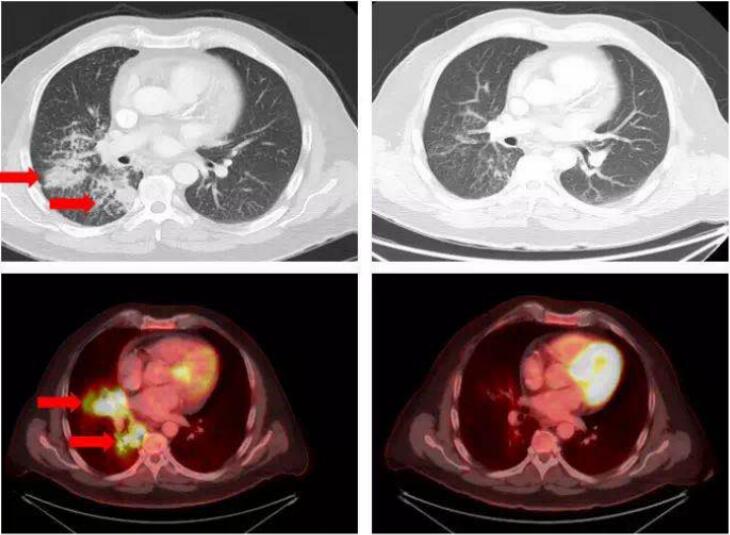

下图为一位中年肺癌缓和,RET-KIF5B融合,使用Retevmo治疗4周之后肿瘤明显缩小。